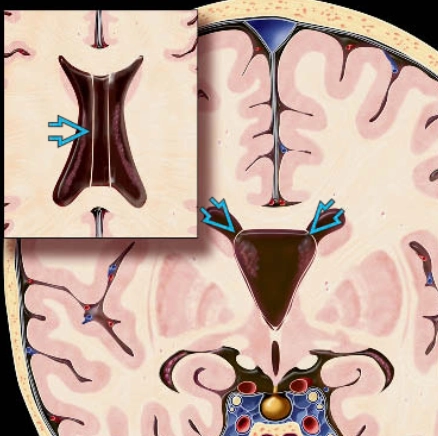

• Dẫn lưu não thất-phúc mạc (Ventriculoperitoneal Shunt - VP)

• Dẫn lưu CSF quá mức (CSF overdrainage)